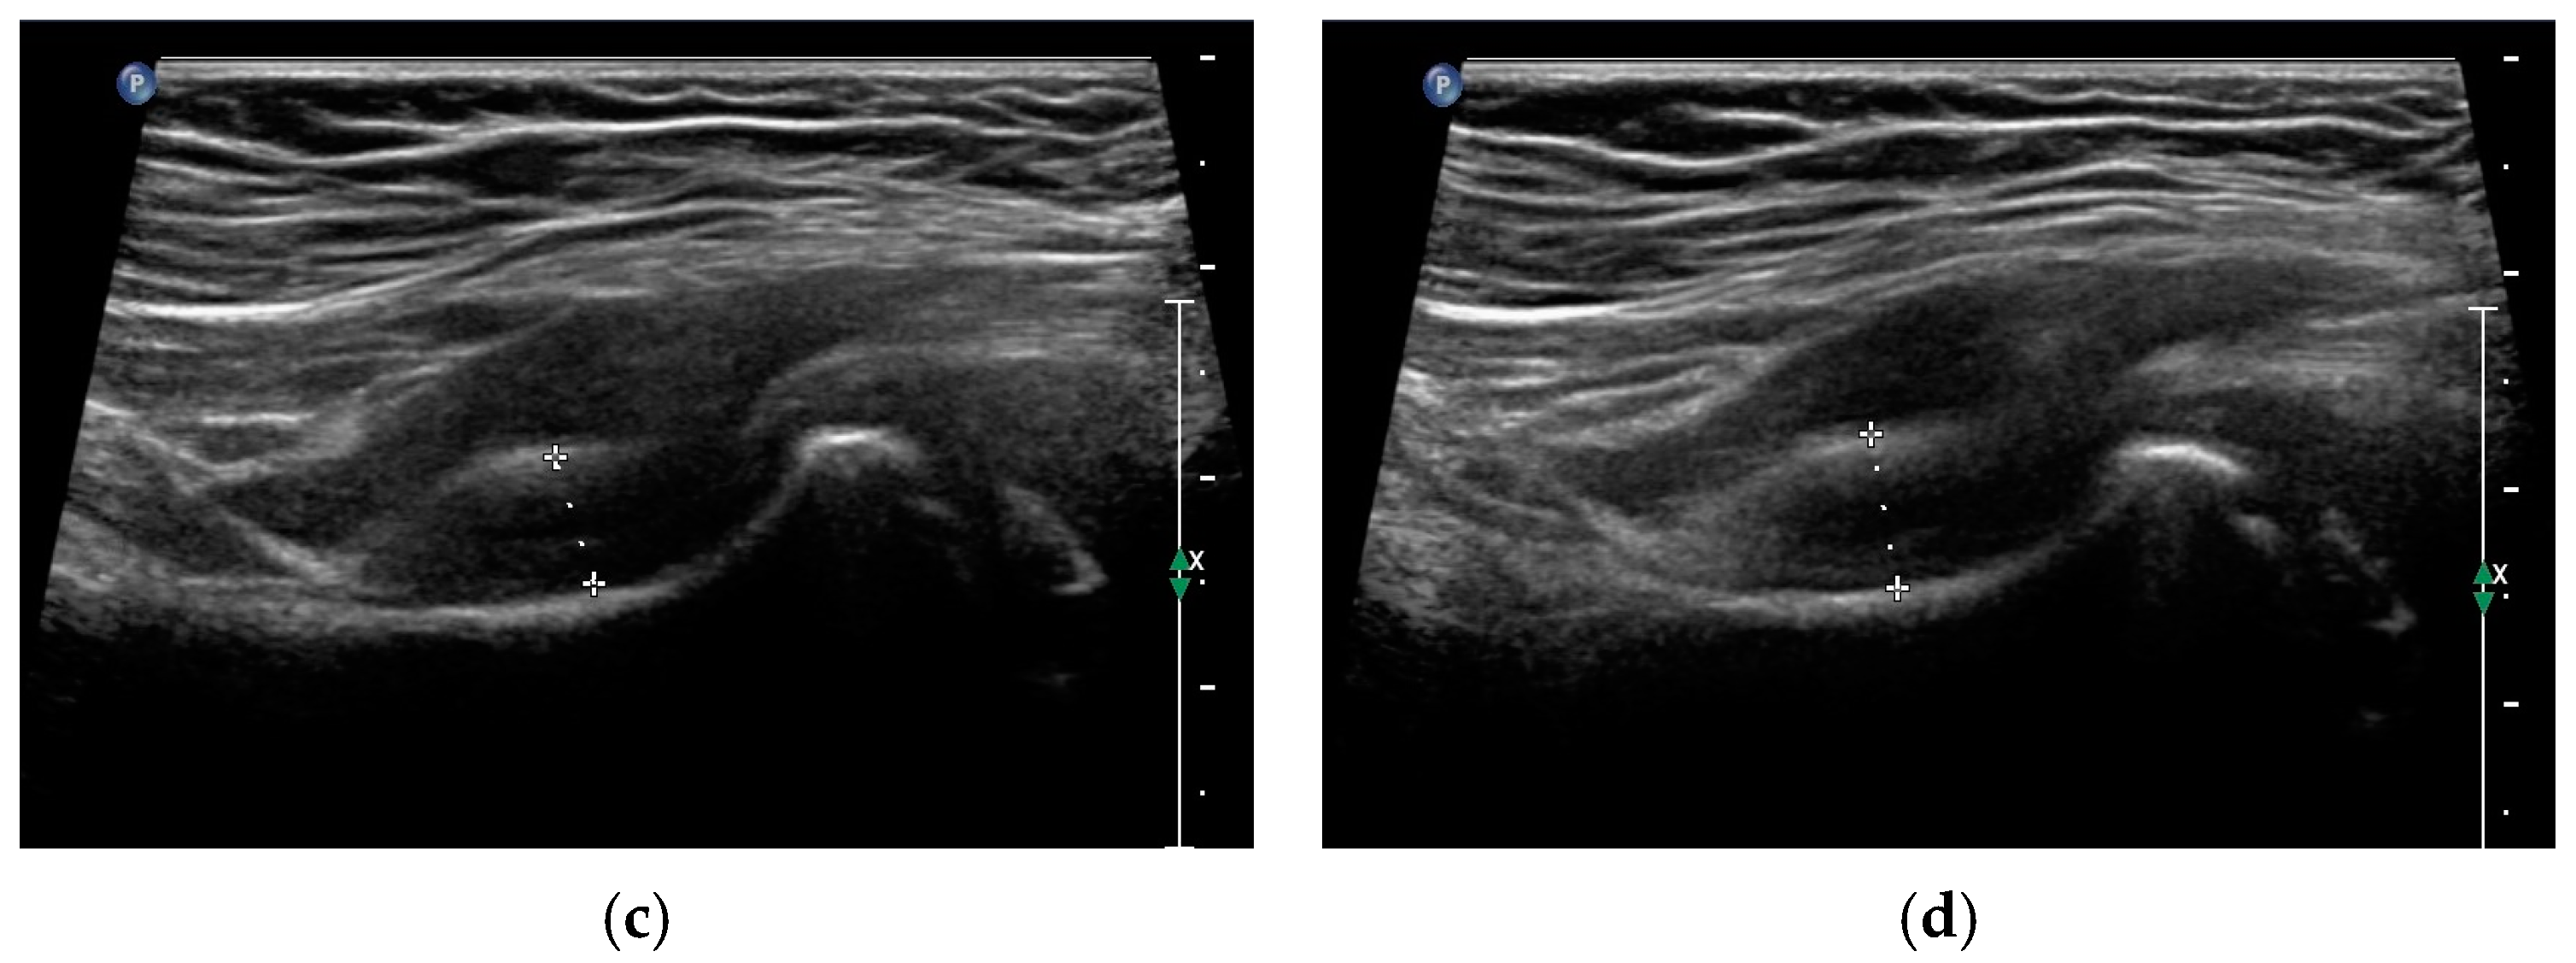

- Maruszczak, K.; Kochman, M.; Madej, T.; Gawda, P. Ultrasound Imaging in Diagnosis and Management of Lower Limb Injuries: A Comprehensive Review. Med. Sci. Monit. 2024, 30, e945413. [Google Scholar] [CrossRef] [PubMed]

- Czyrny, Z. Osgood-Schlatter disease in ultrasound diagnostics—A pictorial essay. Med. Ultrason. 2010, 12, 323–335. [Google Scholar] [PubMed]